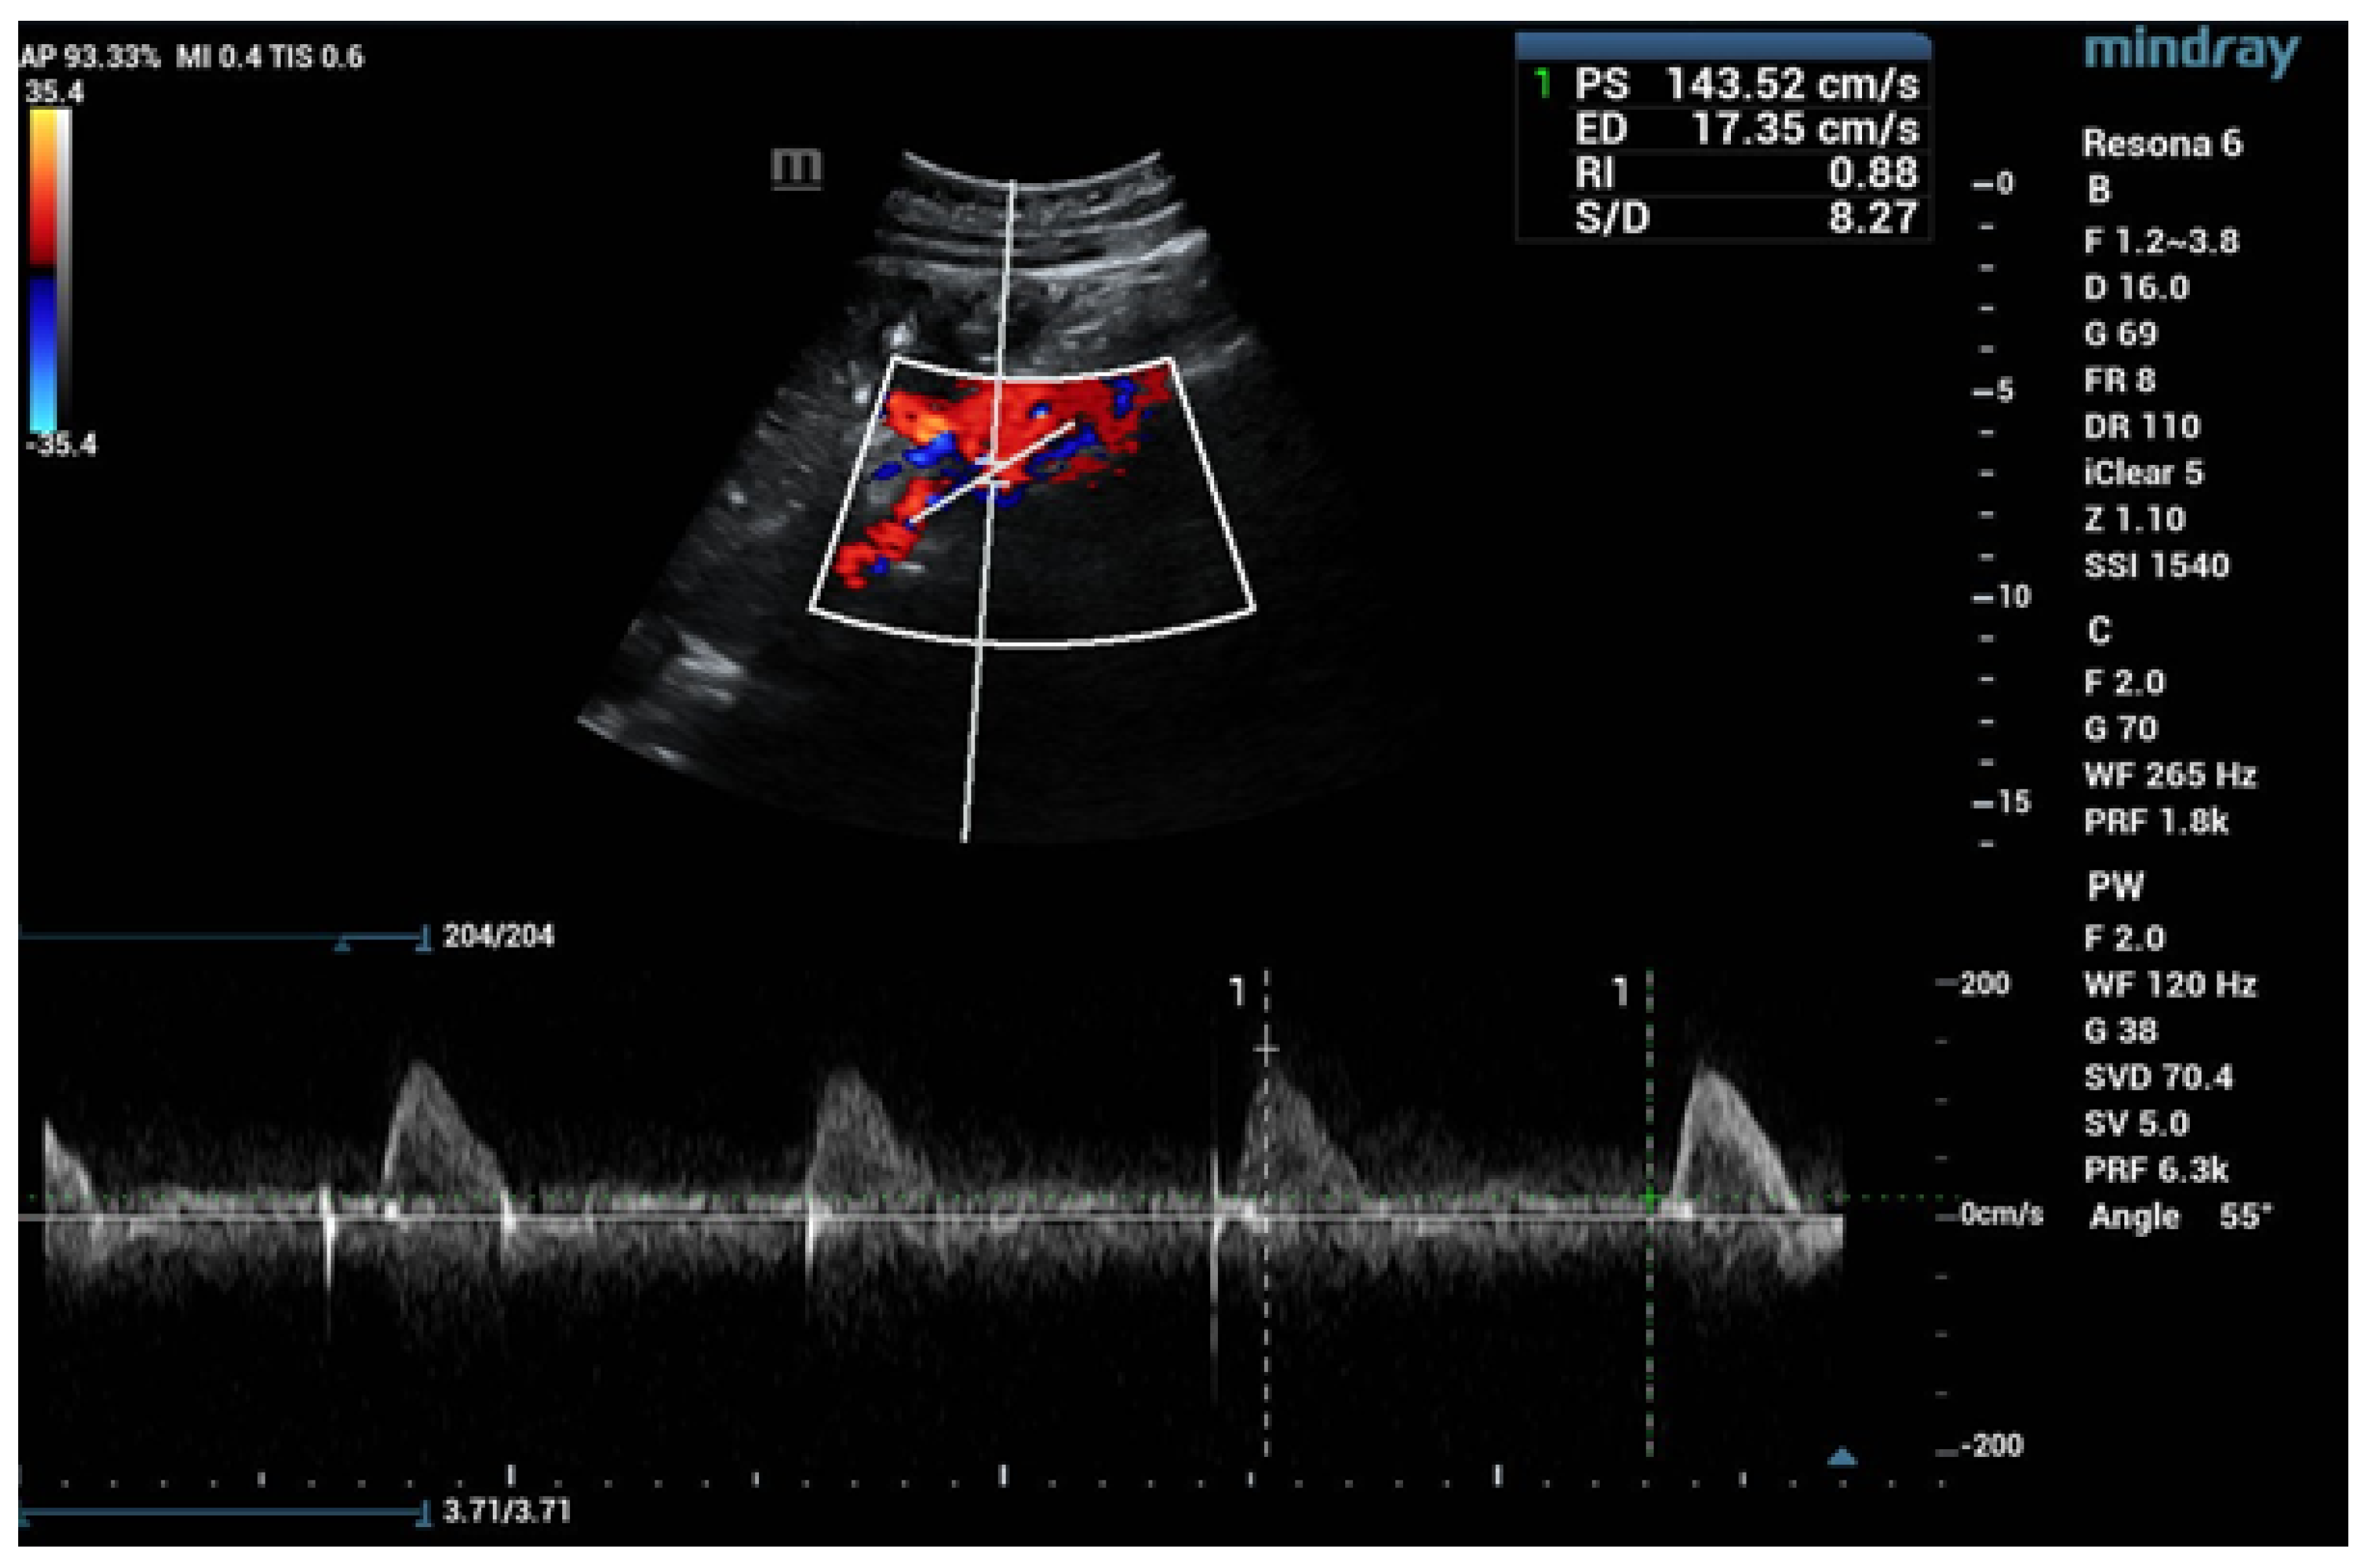

6.1. Ultrasound

- Drelich-Zbroja, A. Polish Society of Ultrasonography Standards—Update: Ultrasound Examination of Renal Arteries. J. Ultrason. 2014, 14, 297–305. [Google Scholar] [CrossRef]

- Stryczyński, Ł. Doppler ultrasound of renal arteries. Arter. Hypertens. Pract. 2022, 8, 186–199. [Google Scholar]

- Saida, K.; Kamei, K.; Hamada, R.; Yoshikawa, T.; Kano, Y.; Nagata, H.; Sato, M.; Ogura, M.; Harada, R.; Hataya, H.; et al. A simple, refined approach to diagnosing renovascular hypertension in children: A 10-year study. Pediatr. Int. 2020, 62, 937–943. [Google Scholar] [CrossRef]

| Normal Value | Parameter |

|---|---|

| 100 cm/s * | PSV (peak systolic velocity) in artery trunk |

| 0.8–1.0 | RAR (renal aortic ratio) in artery trunk |

| ≤70 ms | AT (acceleration time) in intrarenal branches |

| 0.5–0.8 | RI (resistance index) in intrarenal branches |

| 0.78–1.33 | PI (pulsatility index) in intrarenal branches |

| >3 m/s2 | AI (acceleration index) in intrarenal branches |